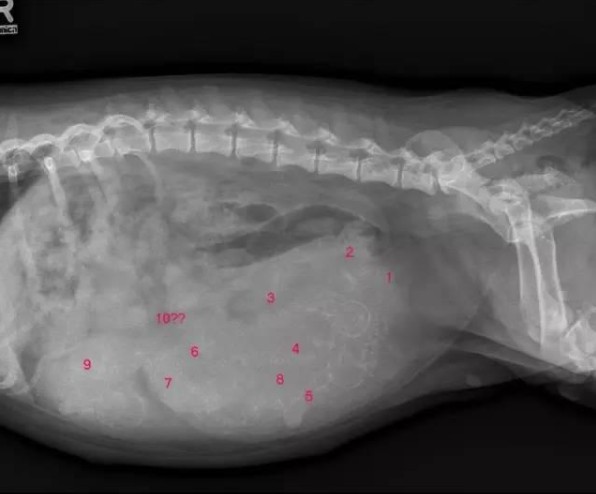

如果家里有未绝育的母狗,它的体型又突然像吹气球那样迅速膨胀,除了是养肥膘,还有可能是怀孕了。狗狗的孕期只有短短的63天,而且怀孕初期并没有明显的症状。因此,在狗狗的发情期后,铲屎官需要时刻关注狗狗是否出现异常,例如情绪波动、乳头变红等。

有些主人发现狗狗疑似怀孕,可能会想着用人类用的验孕棒来给狗狗验孕。但其实,验孕棒是检验不出狗狗怀孕的。因为狗狗和人类是两种不同的物种,两者怀孕出现的物质也是不一样的。如果怀疑狗狗怀孕,最好带它到医院做超声波检查,以免狗狗是假孕。